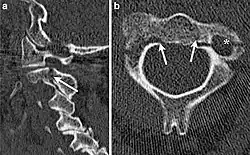

| CT scan of hangman's fracture | |

Hangman's fracture is the colloquial name given to a fracture of both pedicles, or partes interarticulares, of the axis vertebra (C2).[1]